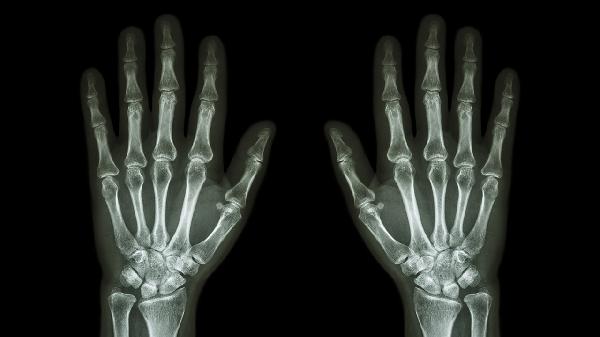

关节软骨退行性病变常见于中老年人群,晨起关节僵硬感明显,X线可见关节间隙狭窄。治疗需联合氨基葡萄糖营养软骨,配合关节腔注射玻璃酸钠改善润滑功能。